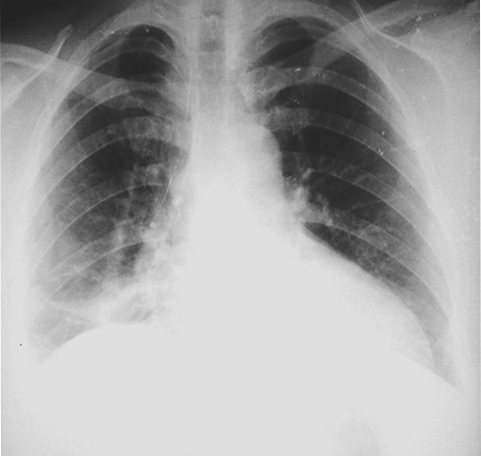

• Radiología del Tórax

Teratoma mediastino, Radiografia PA de Ingreso Teratoma mediastino, Radiografia lateral de Ingreso

Rx. Tórax PA: al momento del Ingreso. Una radiopacidad homogénea densa, redondeada, en hemitorax derecho, para cardiaca, bien limitada, rodeada por parenquima pulmonar sano y no esta adherida al diafragma ni al seno costofrénico derecho el cual se observa libre, pareciendo formar parte con la silueta cardiaca y la altera de manera, como si de una cardiomegalia se tratase. No hay derrame pleural y la conformación de la caja torácica se observa dentro de la normalidad. En la Imagen lateral puede observarse la pared del tumor como una delgada cápsula redondeada superpuesta sobre la silueta cardiaca.